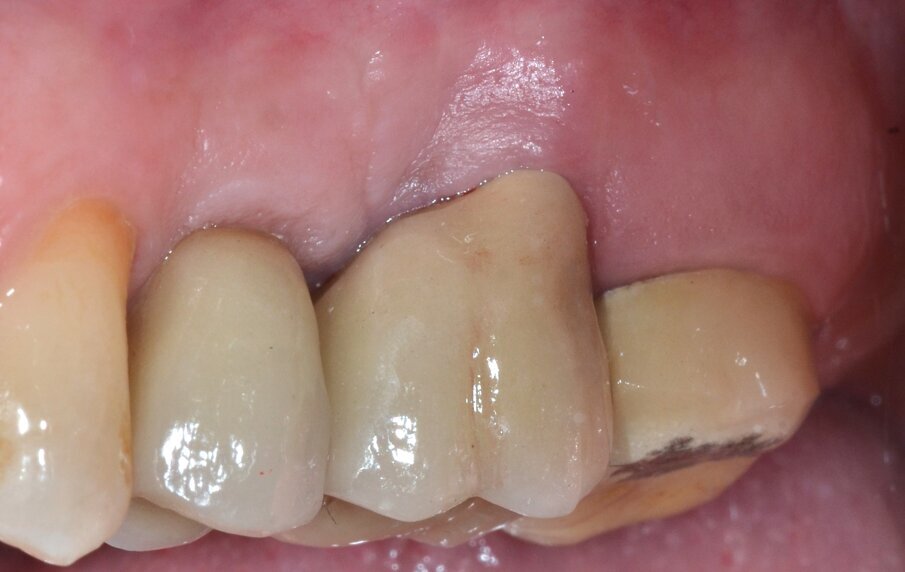

Si procede quindi al recontouring della cresta ossea marginale mediante manovre di osteoplastica e ostectomia allo scopo eliminare i difetti ossei eventualmente presenti e ripristinare un’architettura ossea positiva4. Il lembo buccale viene infine posizionato apicalmente alla cresta ossea e suturato con punti a materassaio ancorati al periostio e punti staccati (Fig. 8) secondo il protocollo di chirurgia parodontale osseo-resettiva5. La finalizzazione protesica del complesso radicolare residuo avviene in accordo con i principi della preparazione differenziata. Dopo un adeguato periodo di guarigione durante il quale l’estetica e la funzione sono garantiti da una corona di tipo provvisorio si procede alla protesizzazione definitiva mediante una corona in metallo-ceramica (Figg. 9, 10). Il follow-up a distanza di 5 anni dall’intervento rivela una soddisfacente integrazione del manufatto protesico con sostanziale stabilità del margine gengivale (Fig. 11) associata a indici biometrici parodontali che rientrano ampiamente in un range fisiologico (Fig. 12) e la completa risoluzione della lesione periapicale

Fig. 11 - Immagine clinica postoperatoria (follow-up a 5 anni).